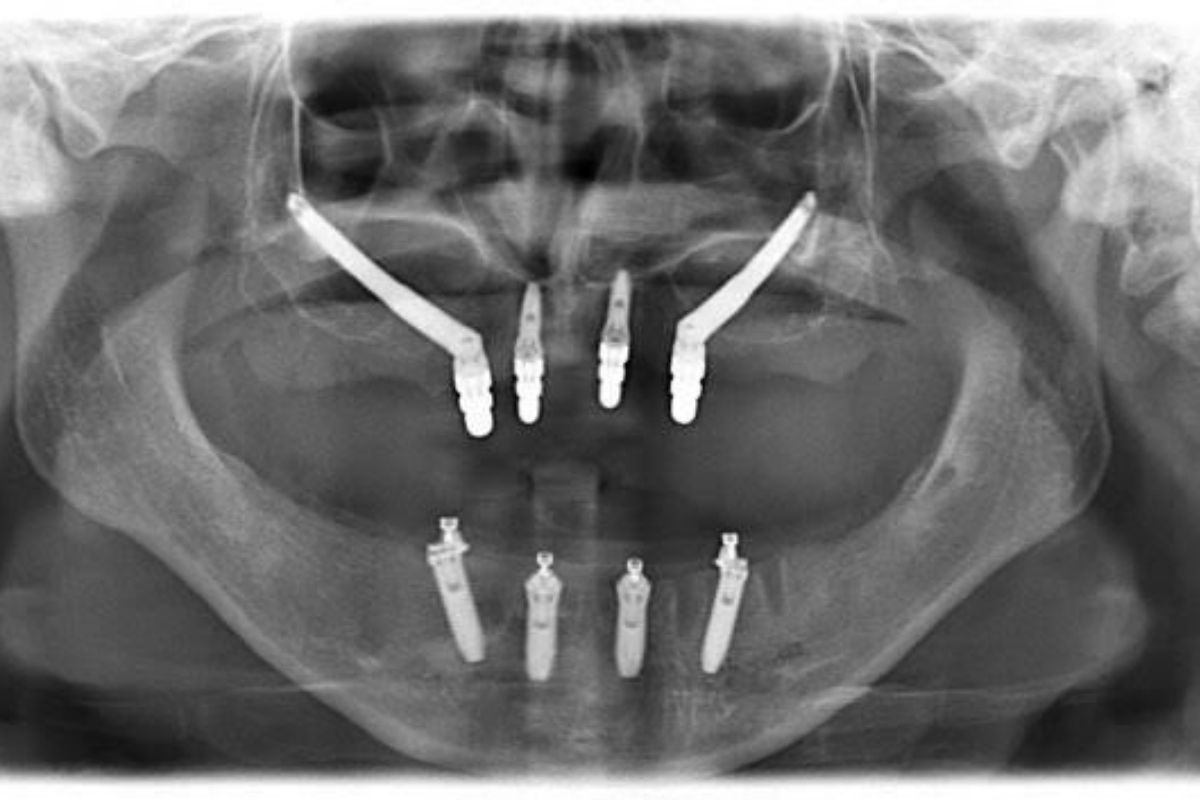

Zygomatic dental implants are a specialized type of implant designed for patients who have experienced significant bone loss in the upper jaw. Unlike traditional dental implants that are placed directly into the jawbone, zygomatic implants are anchored in the cheekbone (zygoma), which has a denser and more stable structure. This makes them an effective solution for patients who have been told they are not suitable candidates for standard implant procedures due to insufficient bone volume.

When asking what are zygomatic implants, it’s important to understand that they are longer than conventional implants and are used in more complex cases. Traditional dental implants typically require adequate bone density or additional procedures like bone grafting or sinus lifts. In contrast, zygomatic bone implants eliminate the need for these extra surgeries, allowing for a faster and more streamlined treatment process often with immediate fixed teeth.

For patients with advanced bone loss, zygomatic implants offer a reliable and life-changing alternative. They are frequently used in full mouth restorations, including treatments like All-on-4, All-on-6, and complete full mouth dental implants. This approach not only restores function and aesthetics but also provides long-term stability, making it one of the most preferred solutions for complex dental cases.

The journey begins with a detailed consultation and advanced 3D imaging, such as a CT scan, to evaluate bone structure and overall oral health. This stage is crucial for understanding whether zygomatic implants are the right solution and for identifying the best placement points in the cheekbone. Based on these findings, a personalized treatment plan is created, often comparing options like All-on-4, All-on-6, full mouth restorations, and traditional dental implants to ensure the most suitable approach for the patient.

During the zygomatic implants surgery, longer implants are carefully placed into the zygomatic (cheek) bone instead of the jawbone. The procedure is typically performed under sedation or general anesthesia to ensure maximum comfort. Because the cheekbone provides strong support, additional procedures such as bone grafting or sinus lifts are usually not required. One of the biggest advantages is that many patients can receive temporary fixed teeth on the same day commonly referred to as “teeth in one day” allowing them to leave the clinic with a functional and aesthetic smile.